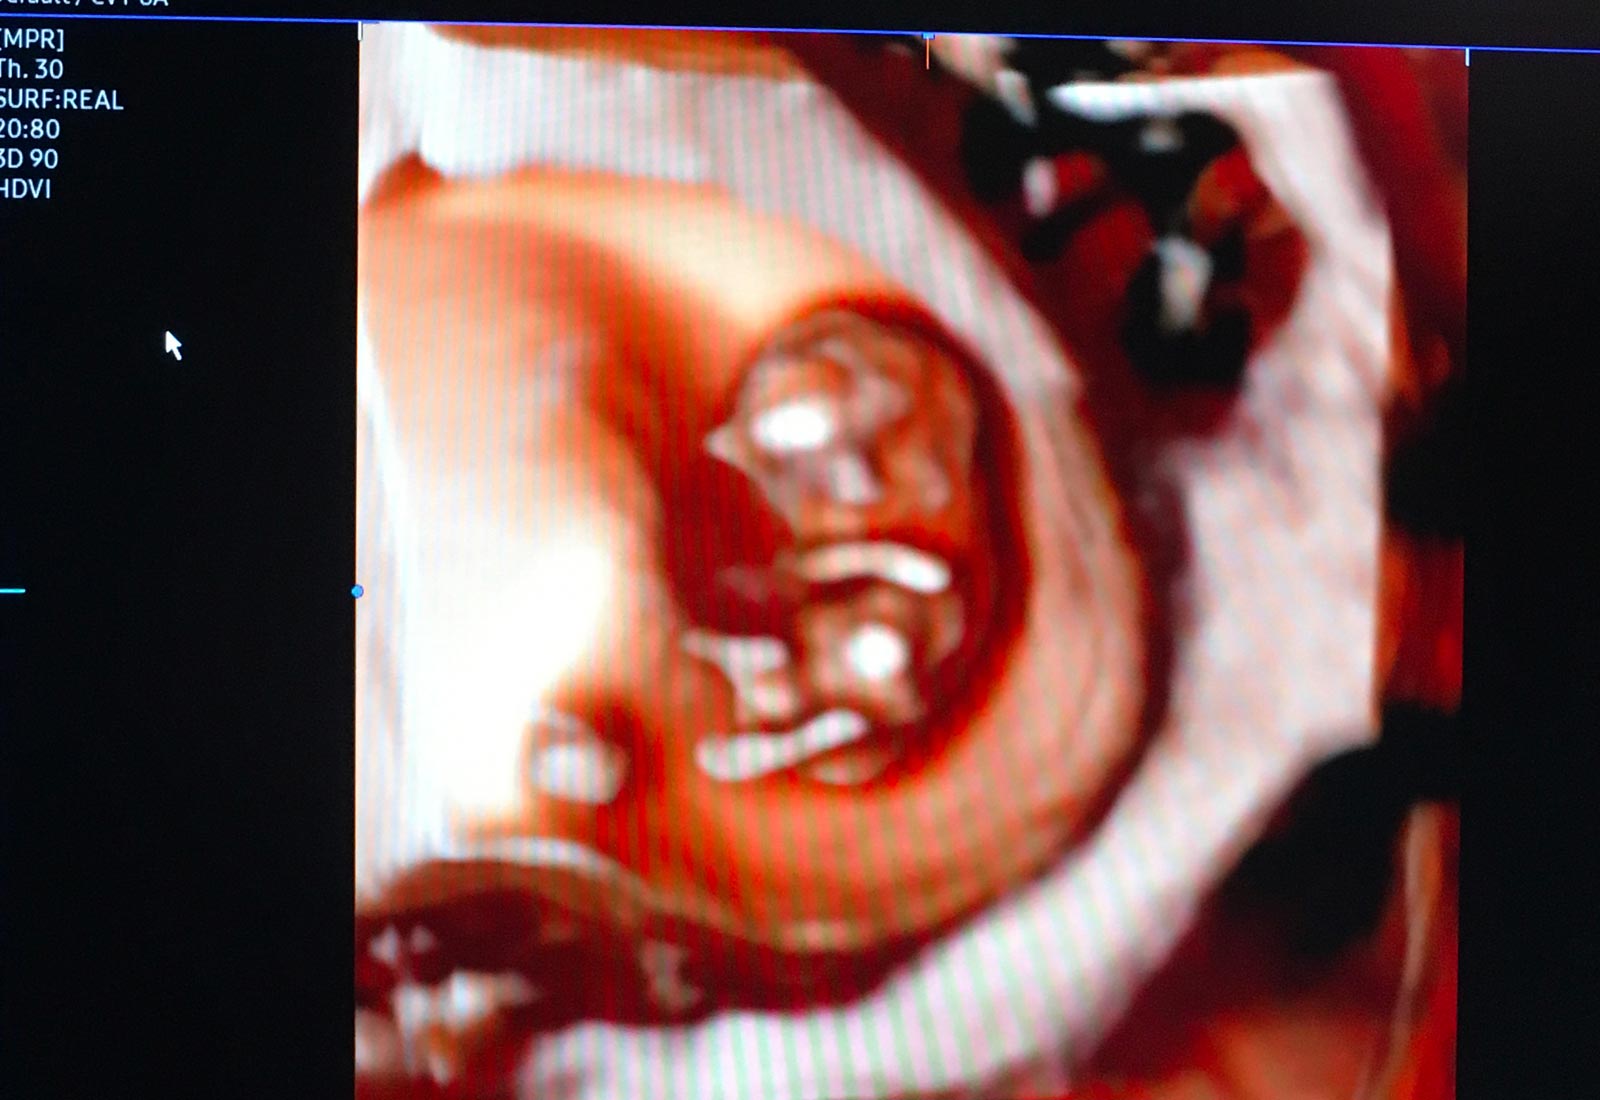

Europa Medica è un Ambulatorio multidisciplinare di Ginecologia, Urodinamica, Urologia e Cardiologia, che offre percorsi diagnostici e terapeutici con tecnologie e standard qualitativi di altissimo livello. Europa Medica nasce con una visione chiara e innovativa del mondo dei servizi privati in sanità: porre il Paziente al centro di tutto, fin dal primo approccio, con cortesia, professionalità e in totale sicurezza. Un Centro di eccellenza unico a Catania, con un team di medici dal profilo professionale di assoluto rilievo. Europa Medica è esperienza, innovazione e buone pratiche, per procedure efficienti e innovative, nelle diagnosi e nelle cure dei pazienti.